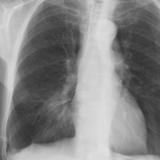

Case 1 PA

Date: 02/28/2004

Views: 3453